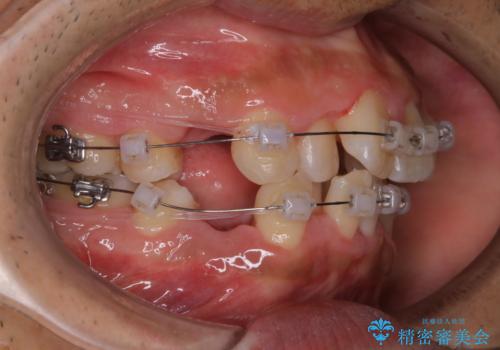

- ワイヤー装置で矯正中の方です。歯磨きがしずらく、専門的な機械でクリーニングしてほしいとの事でした。PMTC60分コースを行いました。

ワイヤー矯正中はブラッシングが難しくなるため、磨き残しが多くなることがあります。適切な道具を使って、適切なブラッシング方法を習得することで、磨き残しを減らすことができます。

また、矯正で歯の移動があると今までなかったところに隙間が出てきたり、ガタつきが解消されてきたりすることで、お口の中の環境が変わります。

矯正治療中も清潔な口腔内を保つことは、とても大切です。そのため、定期的に専門的な機械・材料を使用したProfessinnalcleaning(pmtc)を行うことがおススメです。